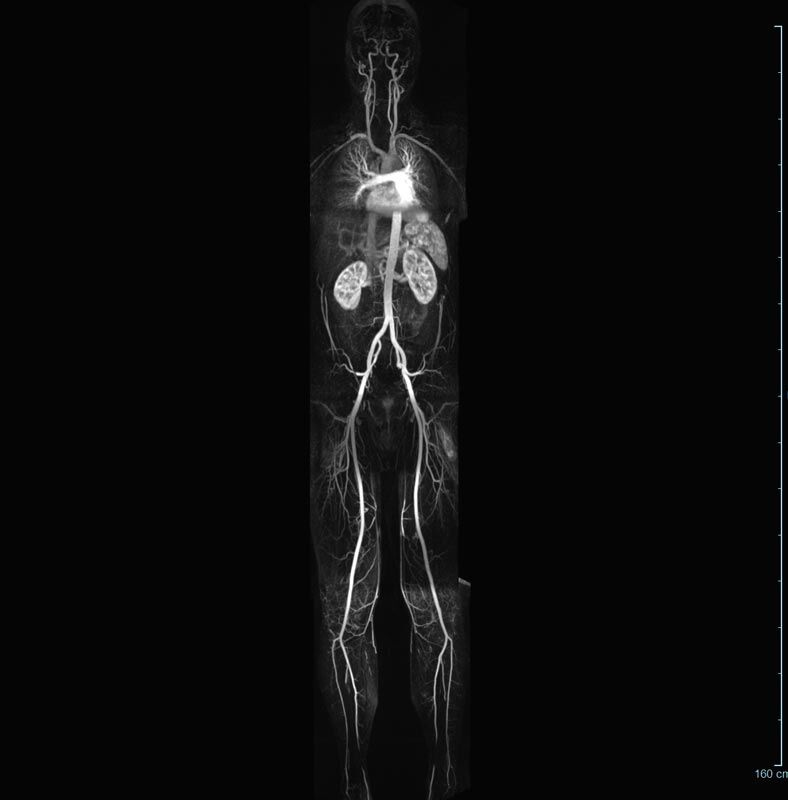

• Bauchgefäße

• Erfassung und Verlaufskontrolle bei arteriellen Aneurysmen (Aussackungen der Arterien), vor allem der Bauchaorta

• Darstellung von Gefäßengen an Nierenarterien, Baucharterien und Becken-/Beinarterien

MR-Angiografie (MRA)

• MR-Angiographie mit Kontrastmittel

• Erfassung arterieller und venöser Gefäße/Bypässe aller Körperregionen mit 3D-Rekonstruktion